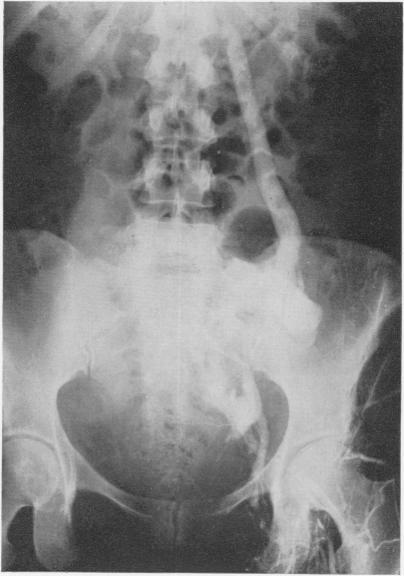

Iliofemoral venous thrombosis. Reappraisal of thrombectomy.

Ann Surg. 1970 Jun;171(6):961-70. doi: 10.1097/00000658-197006010-00018.